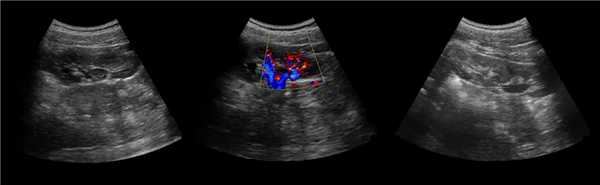

Рисунок. У новорожденного на УЗИ почек определяется гидронефроз (1) и расширенный мочеточник (2) справа. В мочевом пузыре двустороннее уретероцеле (3). При исследовании левой почки структурных изменений не выявлено.

Рисунок. На УЗИ определяется удвоенная чашечно-лоханочная система, расширена лоханка верхнего сегмента (1) и мочеточник на всем протяжение (2, 3), в мочевом пузыре уретроцеле (4). Полное или неполное удвоение чашечно-лоханочной системы возможно увидеть с помощью КТ-урографии.